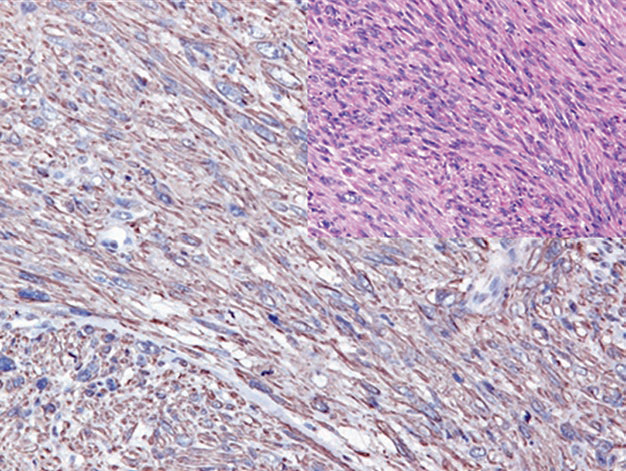

Figure 2. In rhabdomyosarcoma, Myogenin (left) and MyoD1 (right) show strong positive nuclear expression.

It should be noted that both of these myogenic markers can be positive in non-neoplastic myoblasts, which can be seen in reparative and atrophic muscle lesions. Expression of Myogenin and MyoD1 has also been reported in certain other tumors, such as desmoid tumor, infantile fibrosarcoma, and Wilms tumor. In the interpretation of Myogenin and MyoD1 staining, only nuclear staining should be considered positive; other staining patterns (such as cytoplasmic or membranous staining) are diagnostically insignificant artifacts.